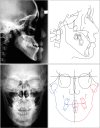

Figure 2

Pretreatment cephalograms.